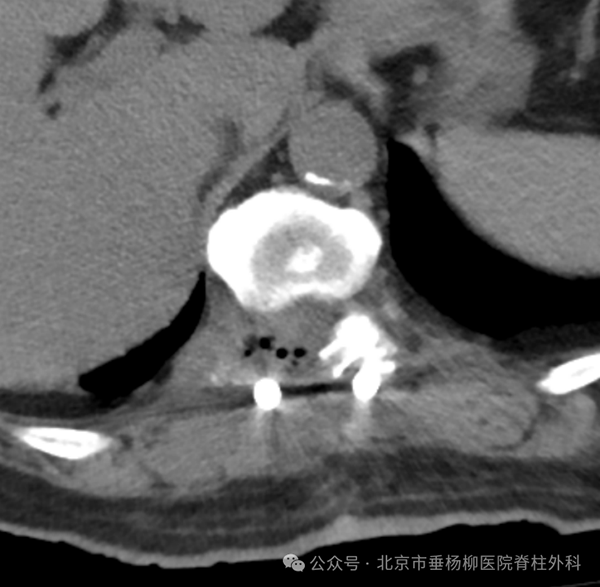

术后复查CT提示肿物已被全部取出。

钛合金内固定物位置良好。